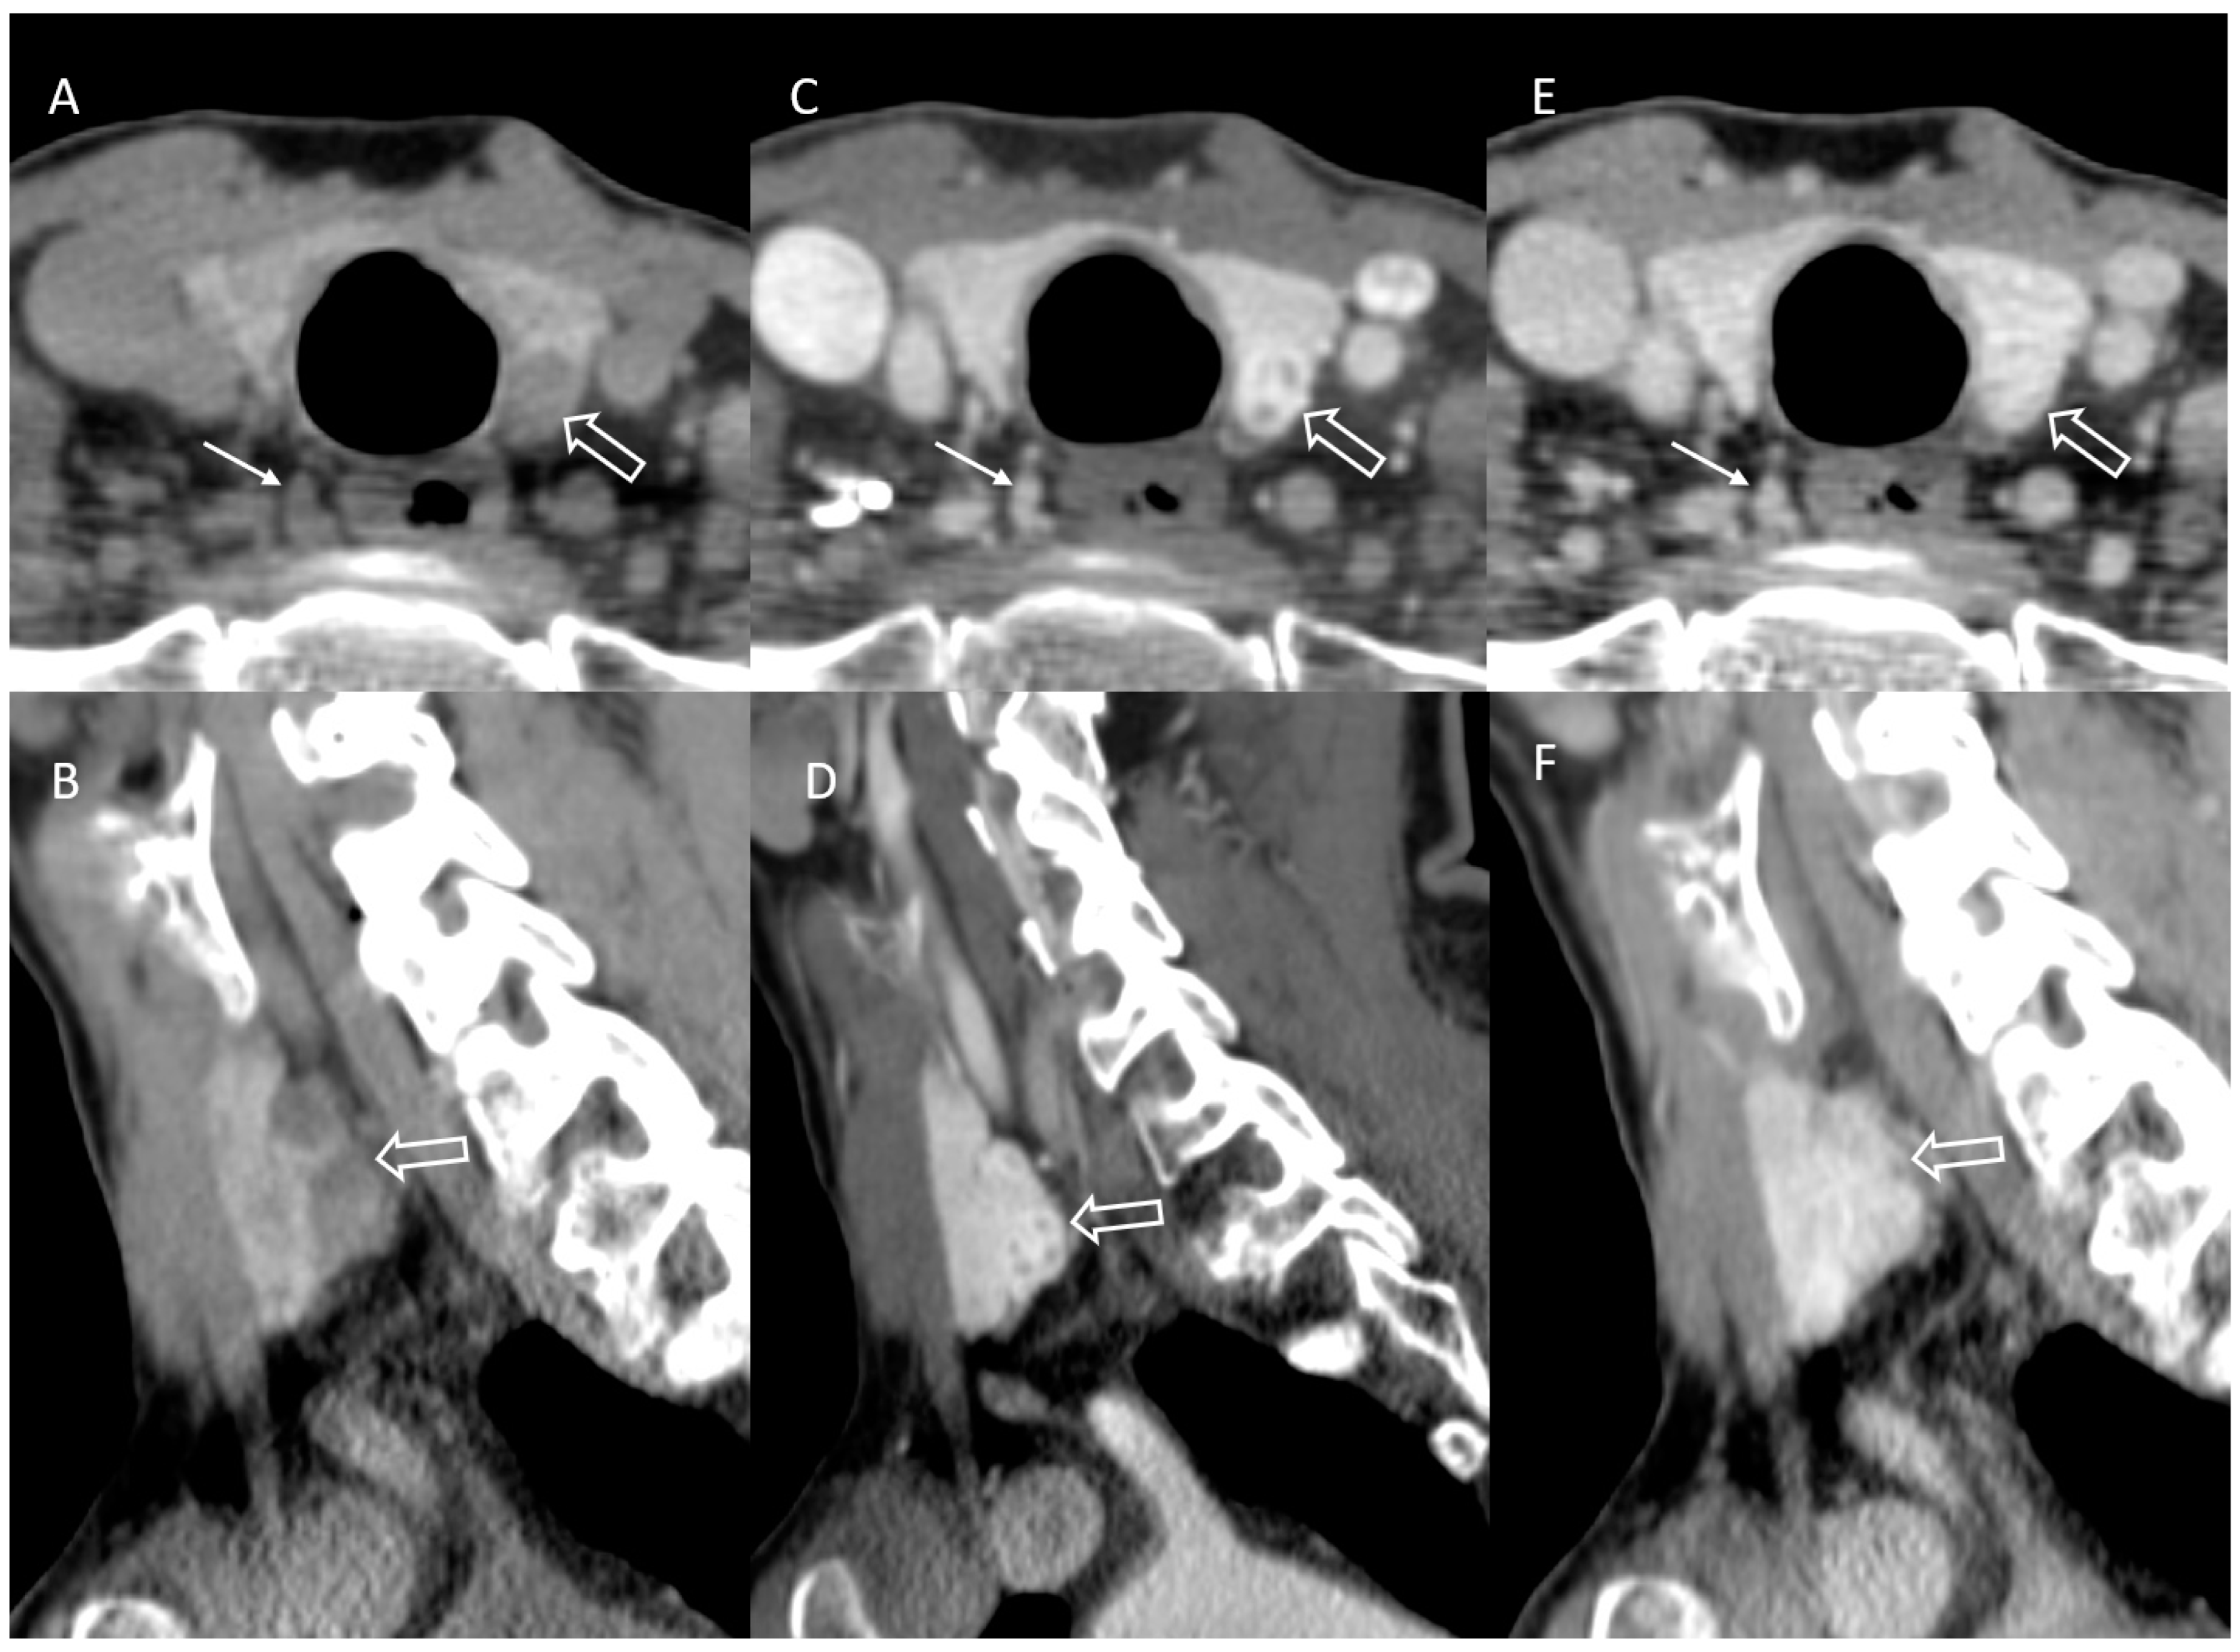

3.5. Multi-Gland Involvement